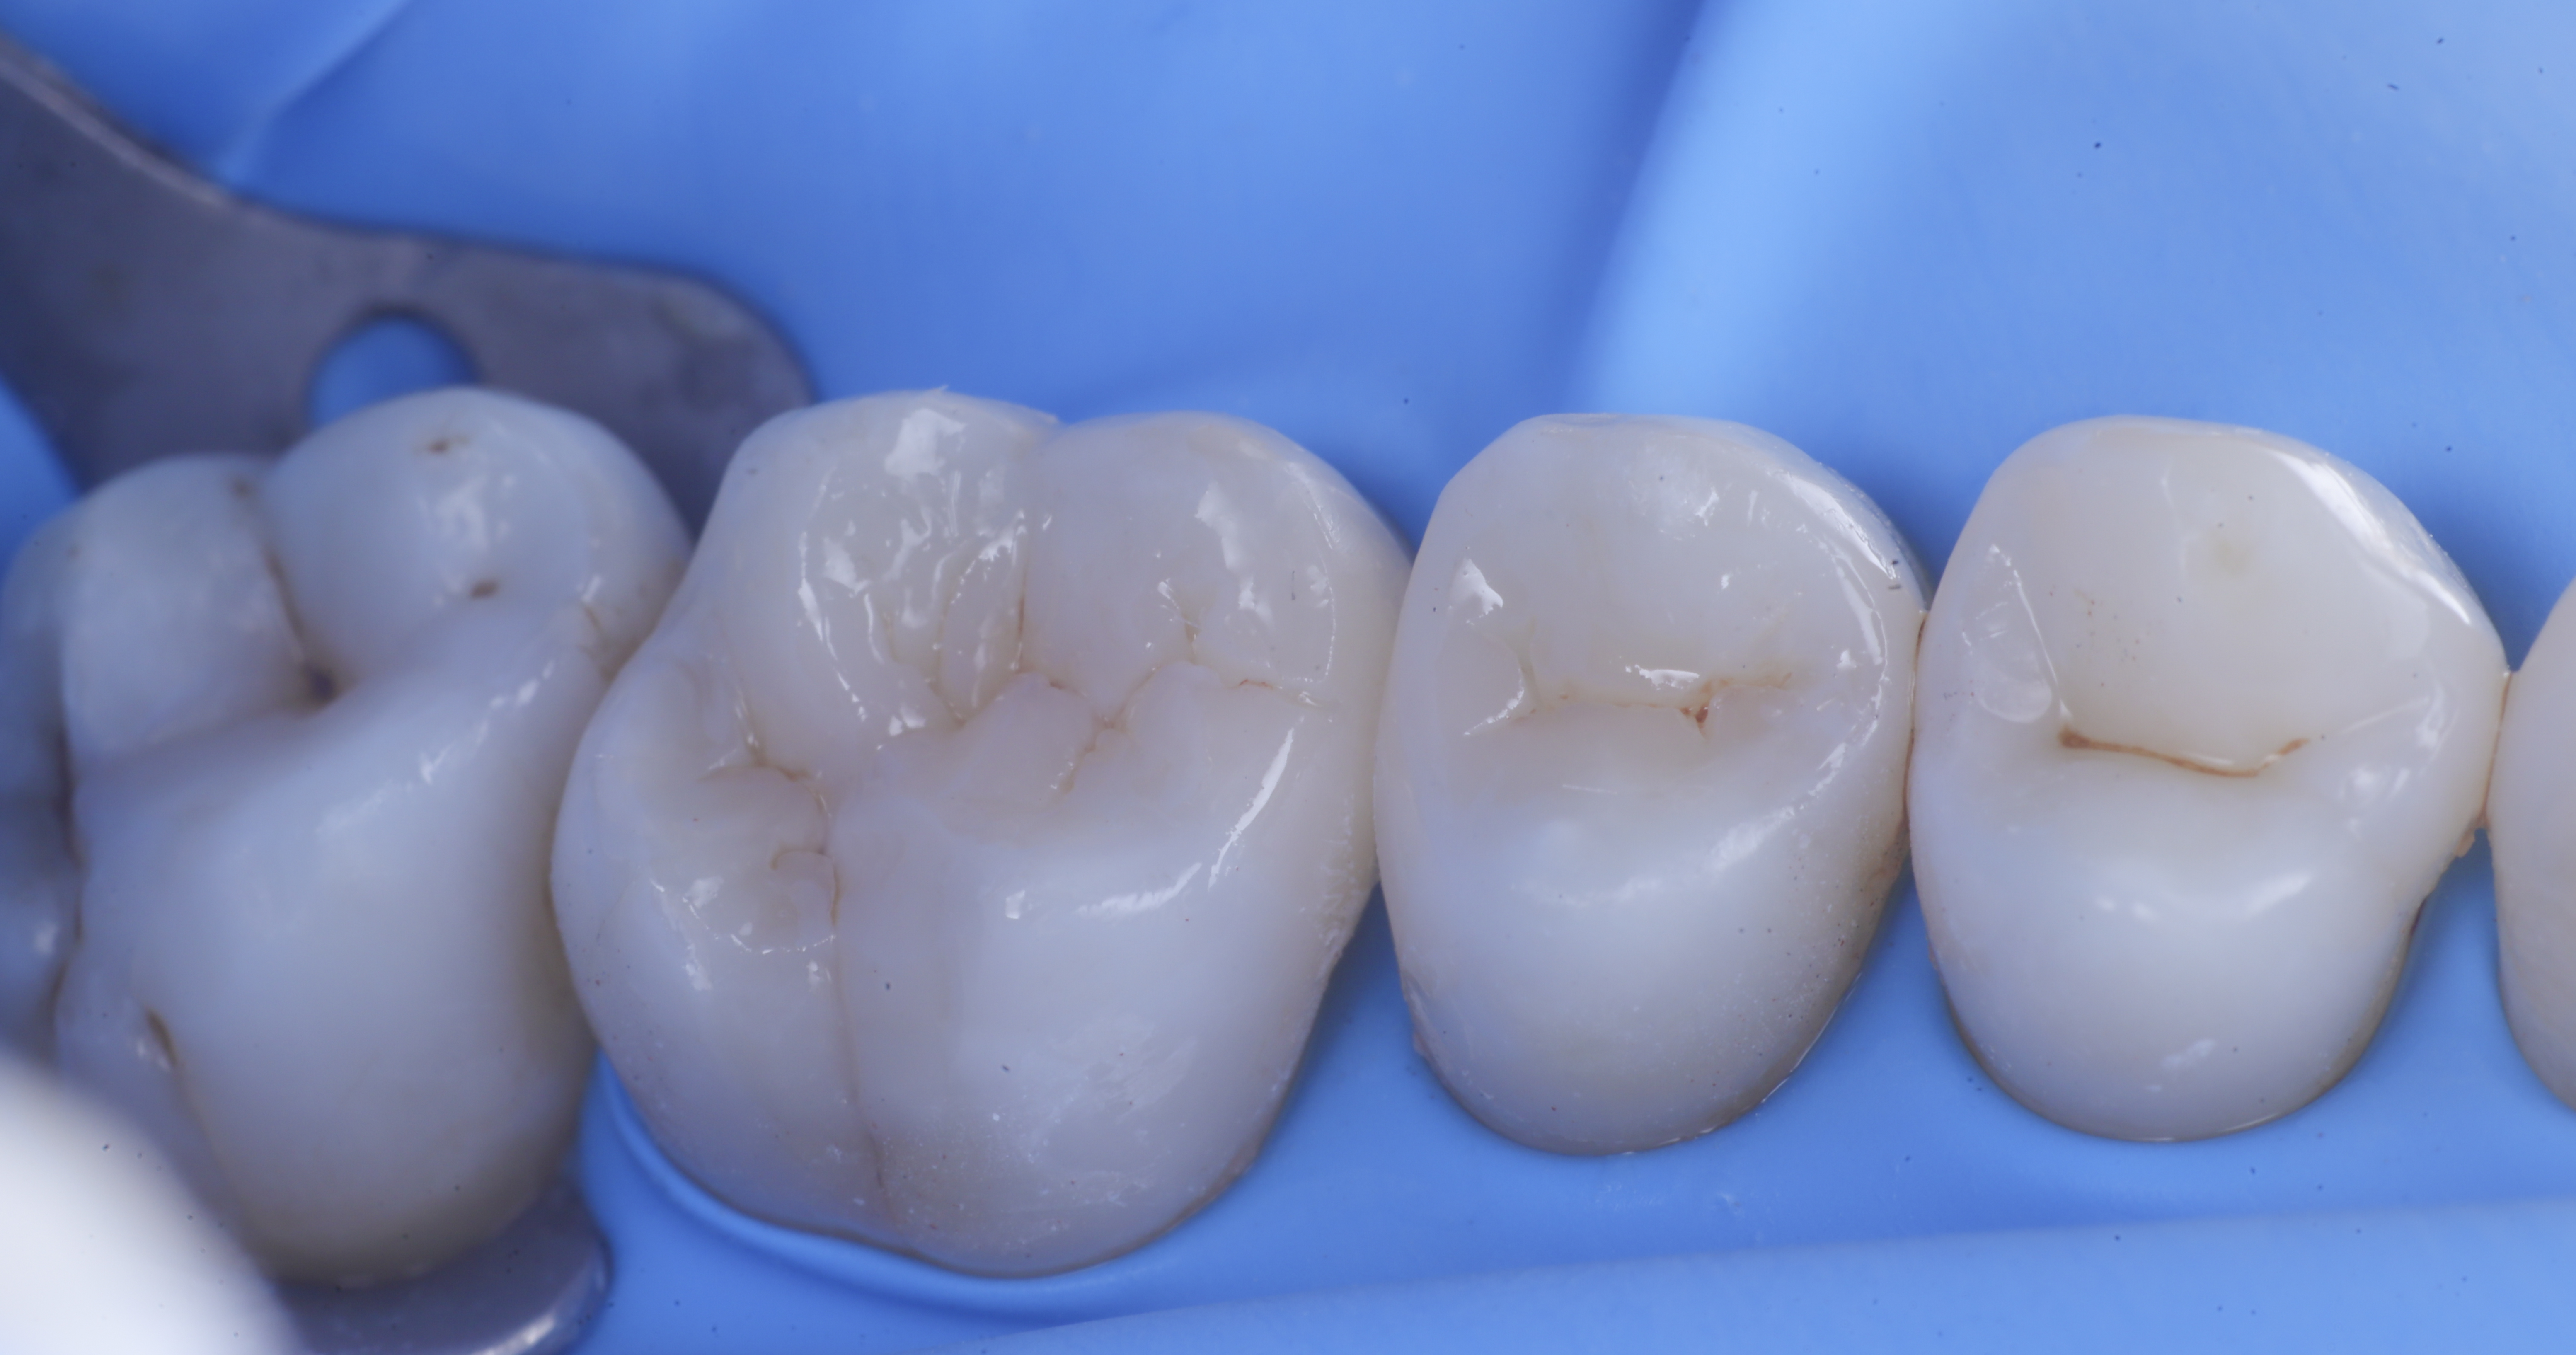

foto 6 Aspetto occlusale delle pareti interprossimali appena create

foto 7 Aspetto vestibolare delle pareti interprossimali appena create